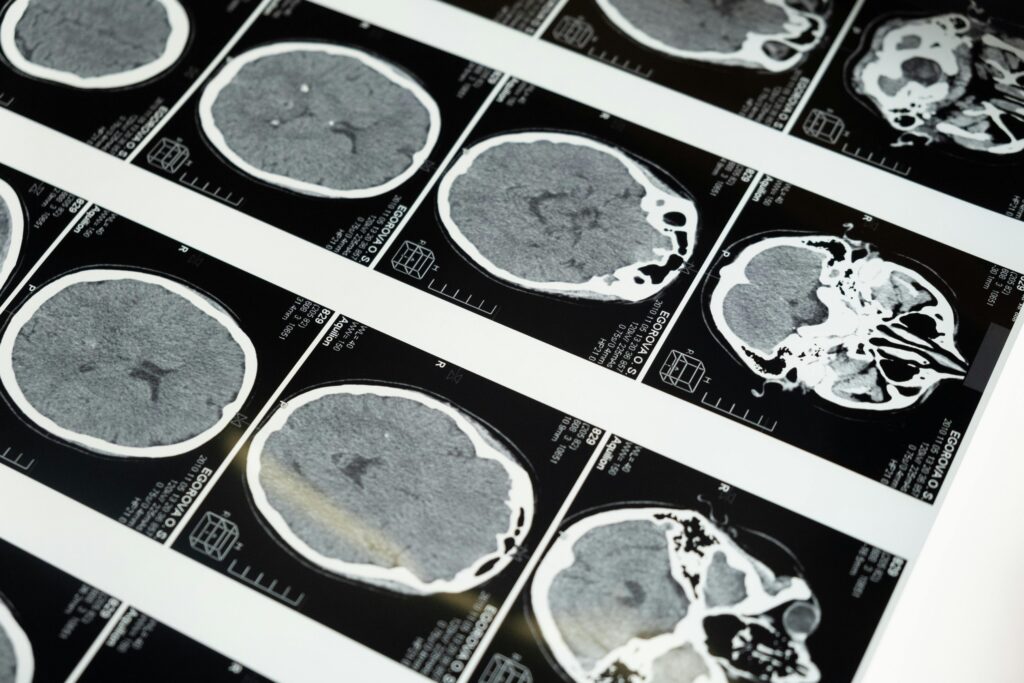

The brain is designed to reinforce behaviors that promote survival, such as eating, bonding, and resting. It does this through the release of dopamine, a neurotransmitter associated with pleasure and motivation. Drugs and alcohol artificially flood the brain with dopamine, creating a powerful surge of reward. This surge is significantly stronger than natural rewards, which makes substances highly reinforcing.

As addiction develops, the brain adapts to repeated exposure. It reduces its natural dopamine production and becomes less sensitive to everyday pleasures. Activities that once brought joy may feel dull or uninteresting. This is a central way how addiction affects the brain and body in North Florida, as individuals begin prioritizing substance use over relationships and responsibilities.

Over time, the brain rewires itself to seek the substance as a primary source of reward. Cravings intensify, and impulse control weakens. Even when someone understands the negative consequences, the drive to use can feel overwhelming. These neurological changes explain why willpower alone is rarely enough to overcome addiction.

Addiction impacts the prefrontal cortex, the area of the brain responsible for decision making and self-regulation. When this region is compromised, judgment becomes impaired. Individuals may engage in behaviors they previously would have avoided. Risk taking increases, and the ability to weigh consequences diminishes.

Understanding how addiction affects the brain and body in North Florida includes recognizing these cognitive shifts. Someone may promise to stop using yet repeatedly return to substances despite serious consequences. This pattern reflects altered brain function rather than intentional disregard for loved ones. The cycle of guilt and relapse often deepens without structured intervention. As the condition progresses, stress responses also become dysregulated. Small challenges can feel overwhelming, increasing the urge to use as a coping mechanism. Treatment helps restore healthier patterns of thinking and emotional regulation. Therapy and medical support work together to strengthen impulse control over time.

Cognitive functions such as memory, concentration, and learning ability can decline with prolonged substance use. Tasks that once felt simple may become difficult. Decision making may feel clouded or slowed. These impairments reflect the neurological impact of addiction.

These changes are not permanent in every case. With sustained sobriety and professional treatment, the brain has the capacity to heal. Neuroplasticity allows new pathways to form over time.